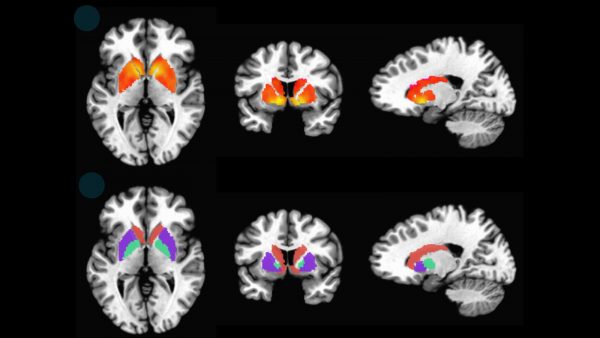

Ερευνητές στην Αυστραλία ανέπτυξαν τεχνολογία mRNA η οποία στοχεύει την τοξική πρωτεΐνη τ η οποία συσσωρεύεται στον εγκέφαλο των ασθενών με Αλτσχάιμερ και άλλες μορφές άνοιας